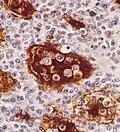

Emperipolesis in Rosai-Dorfman disease highlighted by S-100 staining. -